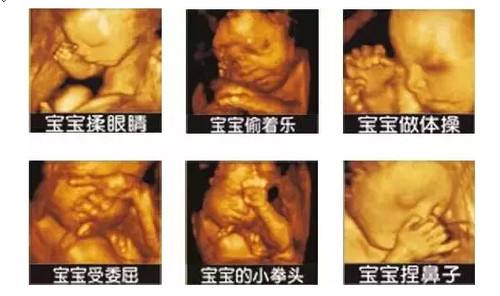

在孕28周左右:此阶段胎儿面部表情也比较丰富,皮下脂肪较以上饱满,胎儿各个部位较前期更加清晰,不仅对以上各类畸形的诊断更加明确,而且胎儿面部的各种表情,如吃手指、喝羊水、打呵欠、哭闹等表情清晰可见。特别是胎儿的某些畸形有可能在中孕晚期或孕晚期才表现出来,所以孕晚期的超声检查是必不可少的。

聊城怀孕做四维彩超的最佳时间?聊城博爱妇女儿童医院医师介绍说四维彩超是目前最先进的彩色超声设备,不仅可以拍摄极为细致的立体、连动的影像,而且能对胎儿早期、中期、晚期的发育状况进行评价,对胎儿的脑组织、肾脏、四肢等器官的生长情况进行观察,对胎儿的异常情况提供准确全面的科学依据。

过去孕妇进行产检基本都采用B超,但B超检查设备,只能检查胎儿的生理指标,四维彩超可以实时的观察人体内部器官的动态运动,它也能够多角度、多方位的观察宫内胎儿的生长发育情况,为早期诊断胎儿先天性体表畸形和先天性心脏疾病,像是唇裂、脊柱裂、 大脑等提供了准确的科学依据。